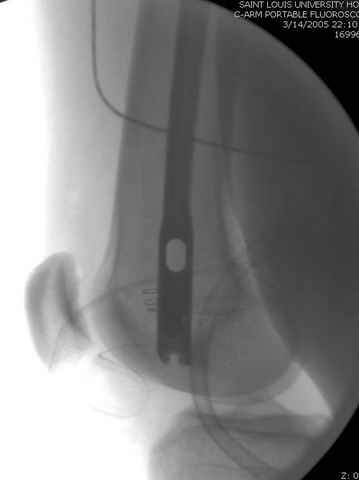

По поводу открытого перелома больной ургентно взят на ретроградное интрамедулярное штифтование, после рутинного дебрайдмента и фасциотомии на бедре и на голени.

интраоперационные

-После мониторинга на компартмент синдром, если давление в компарменте высокое, более 40 мм разницы между диастоличеcким давлением, то фасциотомия.

снимок монитора